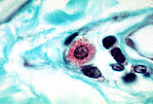

巨细胞

巨细胞由多个上皮样细胞融合而成,胞质融合形成合胞体结构。 |

光镜下,巨细胞的识别依据是其体积巨大,且共同胞质内含有多个细胞核。 |

当细胞核在胞质内随机分布时,该巨细胞称为米勒细胞(Müller)。 |

当细胞核呈环形或马蹄形排列时,该巨细胞称为朗汉斯细胞(Langhans)。 |